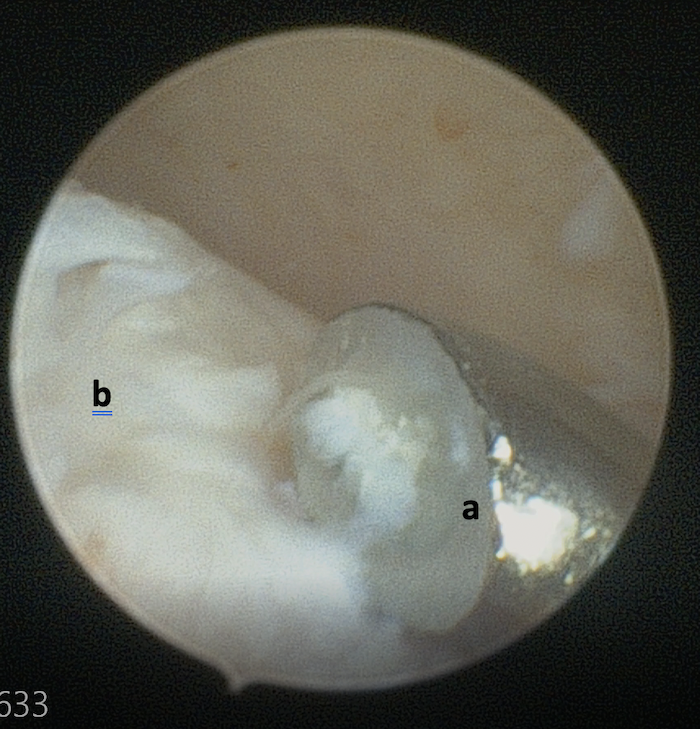

L’arthroscopie met en évidence un large « cratère » en voie de cicatrisation en regard de la face médio-caudale de la tête humérale gauche. Il n’y a pas de fragments visibles dans la gaine du tendon du muscle biceps brachial mais on observe deux larges fragments mobiles d’une taille correspondant au défect cartilagineux précédemment observé en regard du cul de sac caudal de l’articulation. Ces fragments sont calcifiés et mobiles, et semblent correspondre aux éléments observés dans la gaine bicipitale durant le scanner. Cette modification de localisation des fragments est très probablement secondaire à la préparation chirurgicale de la chienne (antérieur gauche tiré en extension) (images 4, 5, 6 et 7).

Image 5 : vue arthroscopique du cul de sac caudal. Large fragment (a). Capsule articulaire (b). Partie caudale de la tête humérale (c).